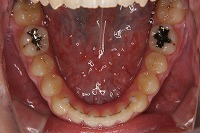

21歳7か月

下顎